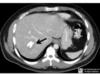

incidental finding of this in 20 yo woman . what to do ?

Focal nodular hyperplasia => observation central stellate scar 가 특징